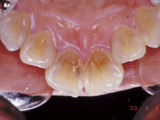

| 他院で矯正治療を受けられましたが、独断でリテーナーの使用を途中でやめてしまったため、歯並びが元に戻ってしまっている患者さんが時々来院されます。 |